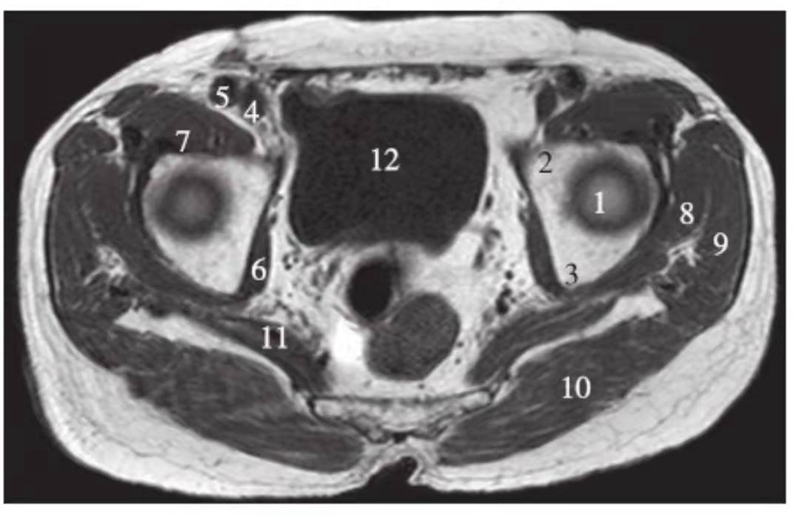

横轴位

正常髋关节股骨头上缘层面T1WI像

1.股骨头;2.耻骨;3.坐骨;4.股静脉;5.股动脉;6.闭孔内肌;7.髂腰肌;8.臀小肌;9.臀中肌;10.臀大肌;11.梨状肌;12.膀胱

正常髋关节经股骨头中心层面T1WI像

1.股骨头;2.耻骨;3.坐骨;4.股静脉;5.股动脉;6.闭孔内肌;7.髂腰肌;8.臀小肌;9.臀中肌;10.臀大肌;11.膀胱